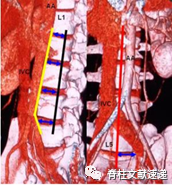

图示:黄线:腹主动脉或左髂血管的左边界;黑线:椎间隙的正前方平面;红线:正中矢状面;蓝色箭头:实际手术窗;AA:腹主动脉;IVC:下腔静脉。